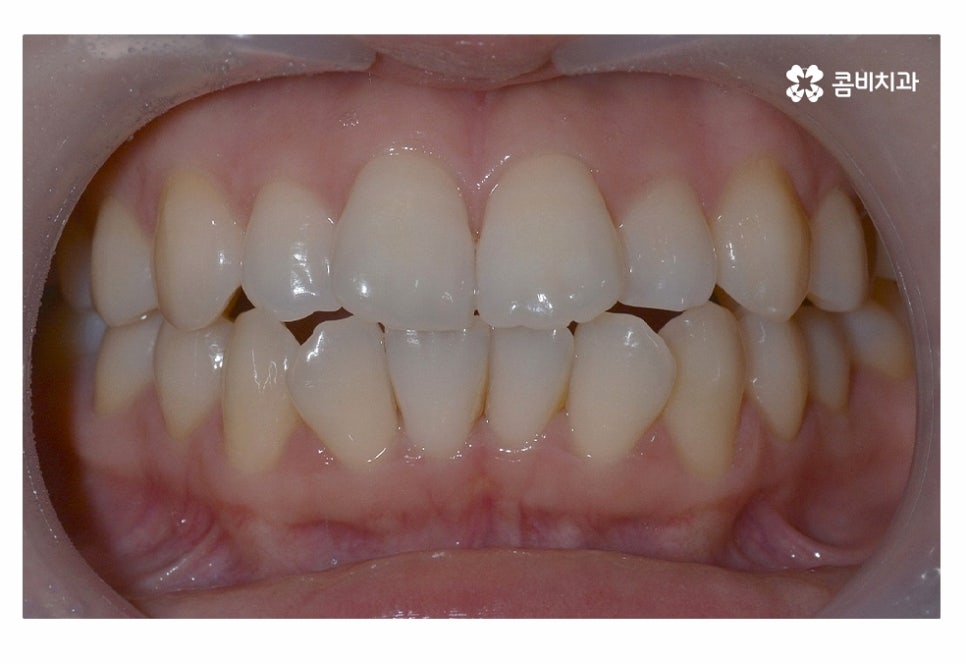

오늘은 치아부분교정 사례와 함께 부분교정에 대한 설명을

해드릴 예정이며 위 사진에서 보시는 환자분의 경우

정면에서 보는 치열과 측면의 차이가 다소 크다는 것을 알 수 있는데요.

이처럼 치열은 정면에서 보이는 것만이 아닌 얼굴형과 골격을

고려하여 치료 계획을 세워야 한다는 것을 알 수 있어요.